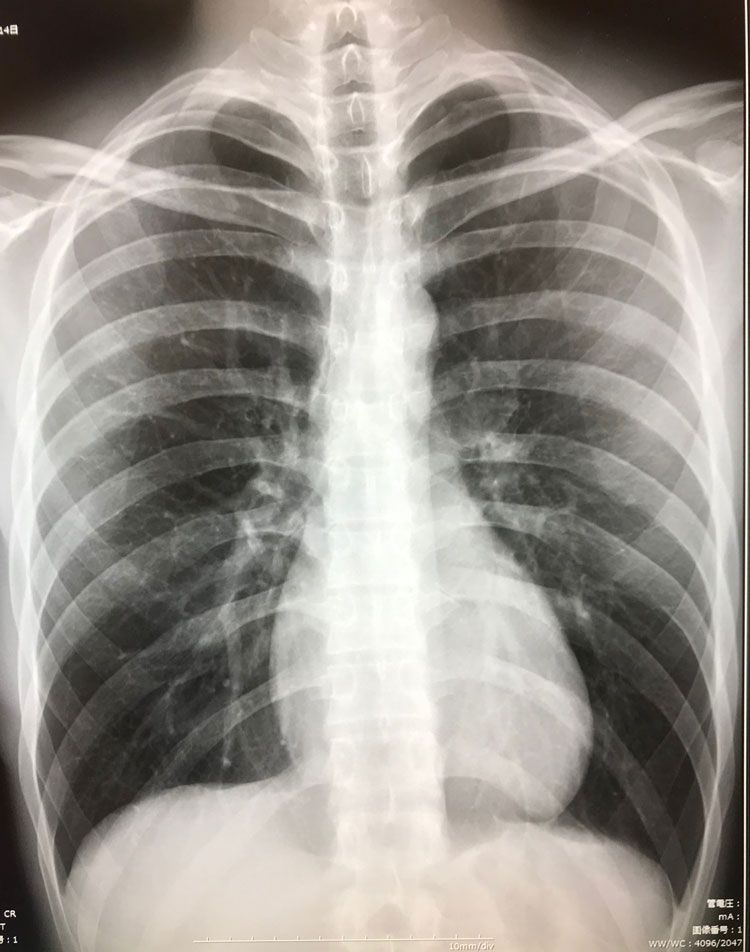

レントゲン

当院のデジタルX線撮影装置は、X線撮影画像を瞬時に処理し即座に画像表示することができます。

瞬時に診断画像を表示できますので、患者様の検査時間を約4分の1に短縮できます。また、従来のX線撮影に比べて約半分の被ばく線量できめ細かな診断画像を作成できるため、患者様の負担を大幅に低減することができます。

胸部レントゲン写真には肺にある骨に重なった病変が見やすくなる画像処理技術(Bone Suprpession)を導入し、診断の精度向上に役立てております。